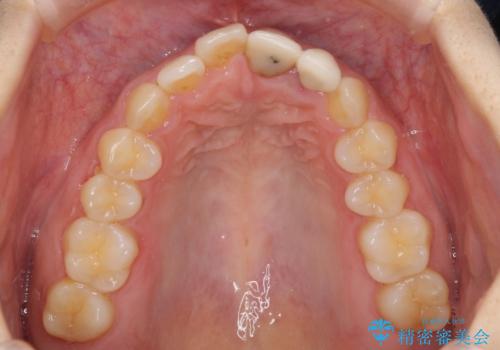

既にクラウンが装着されていた歯は歯根の先端に病変が認められたため、根管治療を行うこととしました。

仮歯装着の時点で自然な見た目となり、オールセラミッククラウンを装着した際には、まるで自分の歯のようと喜んでくださいました。

長年変色を気にしており、もっと早くに治療を行えば良かったとおっしゃっていました。